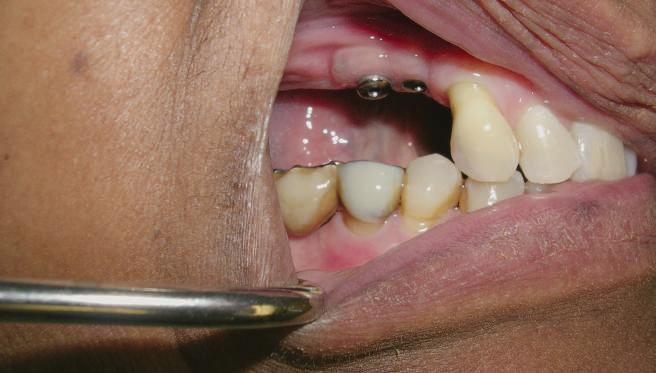

Reprepararea intraorală a bonturilor Acest pacient prezenta dentiţia maxilară compromisă, refuzând proteza mobilizabilă. Prin abordarea în etape, se menţin o parte din bonturile dentare naturale; s-a observat recesie în momentul amprentării pentru cel de-al doilea grup de implanturi.

Fig. 1 prezintă pacientul după inserarea primului set de bonturi implantare individualizate; dinţii naturali adiacenţi

sunt încă prezenţi pentru a susţine puntea provizorie.

Şapte luni mai târziu (fig. 2), acele bonturi individualizate din prima etapă au manifestat semne de recesie de 1-3mm. Atitudine: S-a decis reprepararea intraorală a tuturor bonturilor (fig. 3), astfel încât toate marginile bonturilor să fie la nivelul sau sub marginea gingivală (de notat că 1.1. şi 2.1. au fost submersaţi ulterior pentru a avea sprijin implantar deplin).

Deşi reprepararea a îmbunătăţit marcat estetica finală, a necesitat aplicarea şnurului de retracţie, amprente noi şi turnări noi.

Un caz separat dar similar ilustrează în figurile 4 și 5 reprepararea intraorală a bontului.

Cazul (1): Reprepararea intraorală a bonturilor Figurile

1. Aspect după inserarea primului set de bonturi implantare individualizate.

2. După 7 luni, bonturile individualizate din prima etapă au prezentat recesie de 1-3mm.

3. Bonturile repreparate intraoral.

Alt caz (1) Figurile

4. După osteointegrarea implantului 2.4., s-a observat recesia în etapa de amprentare a implantului 2.5.; s-a decis reprepararea marginilor bontului individualizat CAD/CAM 2.4. Înainte de preparare s-a aplicat şnur de retracţie pentru a evita lezarea ţesutului şi a îmbunătăţi vizibilitatea dintelui 2.3. şi a marginii bontului implantar individualizat. Aşa cum era de aşteptat, recesia a fost mai mare de-a lungul versantului distal al bontului 2.4. adiacent locului de extracţie vindecat/cu implantul mai nou.

5. Bontul individualizat aplicat (2.5.) cu bontul repreparat anterior (2.4.). Nu a survenit recesie nouă de o perioadă de peste 3 ani.